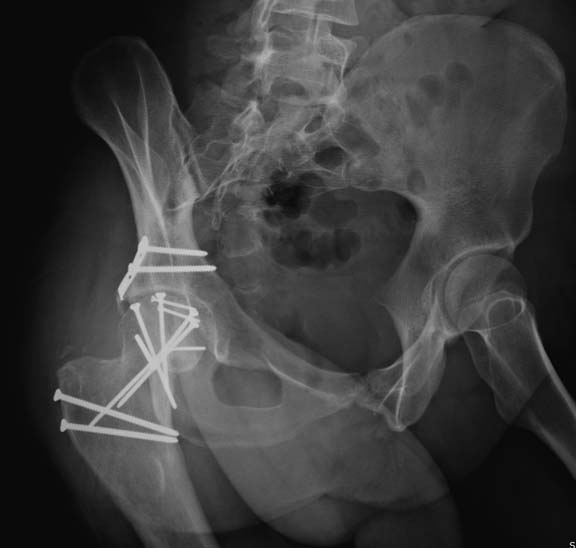

Здесь клинические примеры: Первый случай передний доступ, второй с ICP

monitor Flipp Trochanteris

и с переломом заднего края.